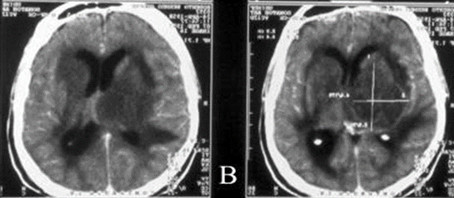

TAC de cráneo inicial: se observó imagen heterogénea predominantemente isodensa, con densidades entre 15 y 44 UH, paraventricular izquierda; interesa los núcleos basales y mide 64 x 41 x 63 mm, rodeada de área hipodensa cuyos contornos laterales presentaban el aspecto de dedo de guante, lo que sugirió edema vasogénico asociado. La lesión tenía carácter expansivo, desplazaba las estructuras de la línea media más aproximadamente 10 mm y colapsaba el ventrículo lateral ipsilateral. (Fig. 1)

RM 29 días después: en comparación con estudios previos hay mejoría del cuadro, consistente en disminución del tamaño de la lesión reportada, así como del edema subyacente. Con respecto a la anterior no se observa colapso del sistema ventricular ni desplazamiento de las estructuras de la línea media. (Fig. 2)